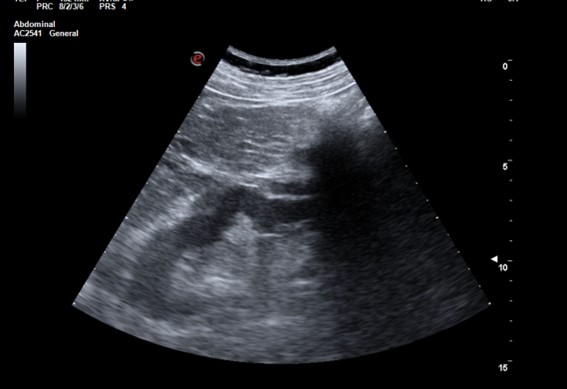

Descripción de los hallazgos ecográficos y las imágenes más relevantes para la resolución del caso.